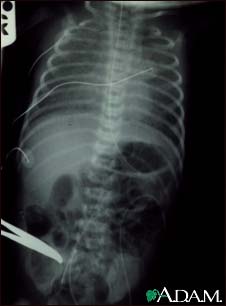

Totally anomalous pulmonary venous return, X-ray

Totally anomalous pulmonary venous return (TAPVR) is a form of congenital heart disease.